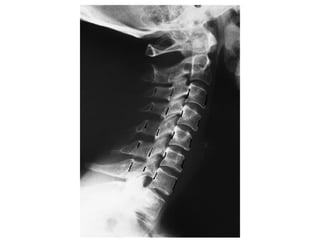

• Investigations

– Confirmatory

• Xrays

• CT

• MRI

• Myelography